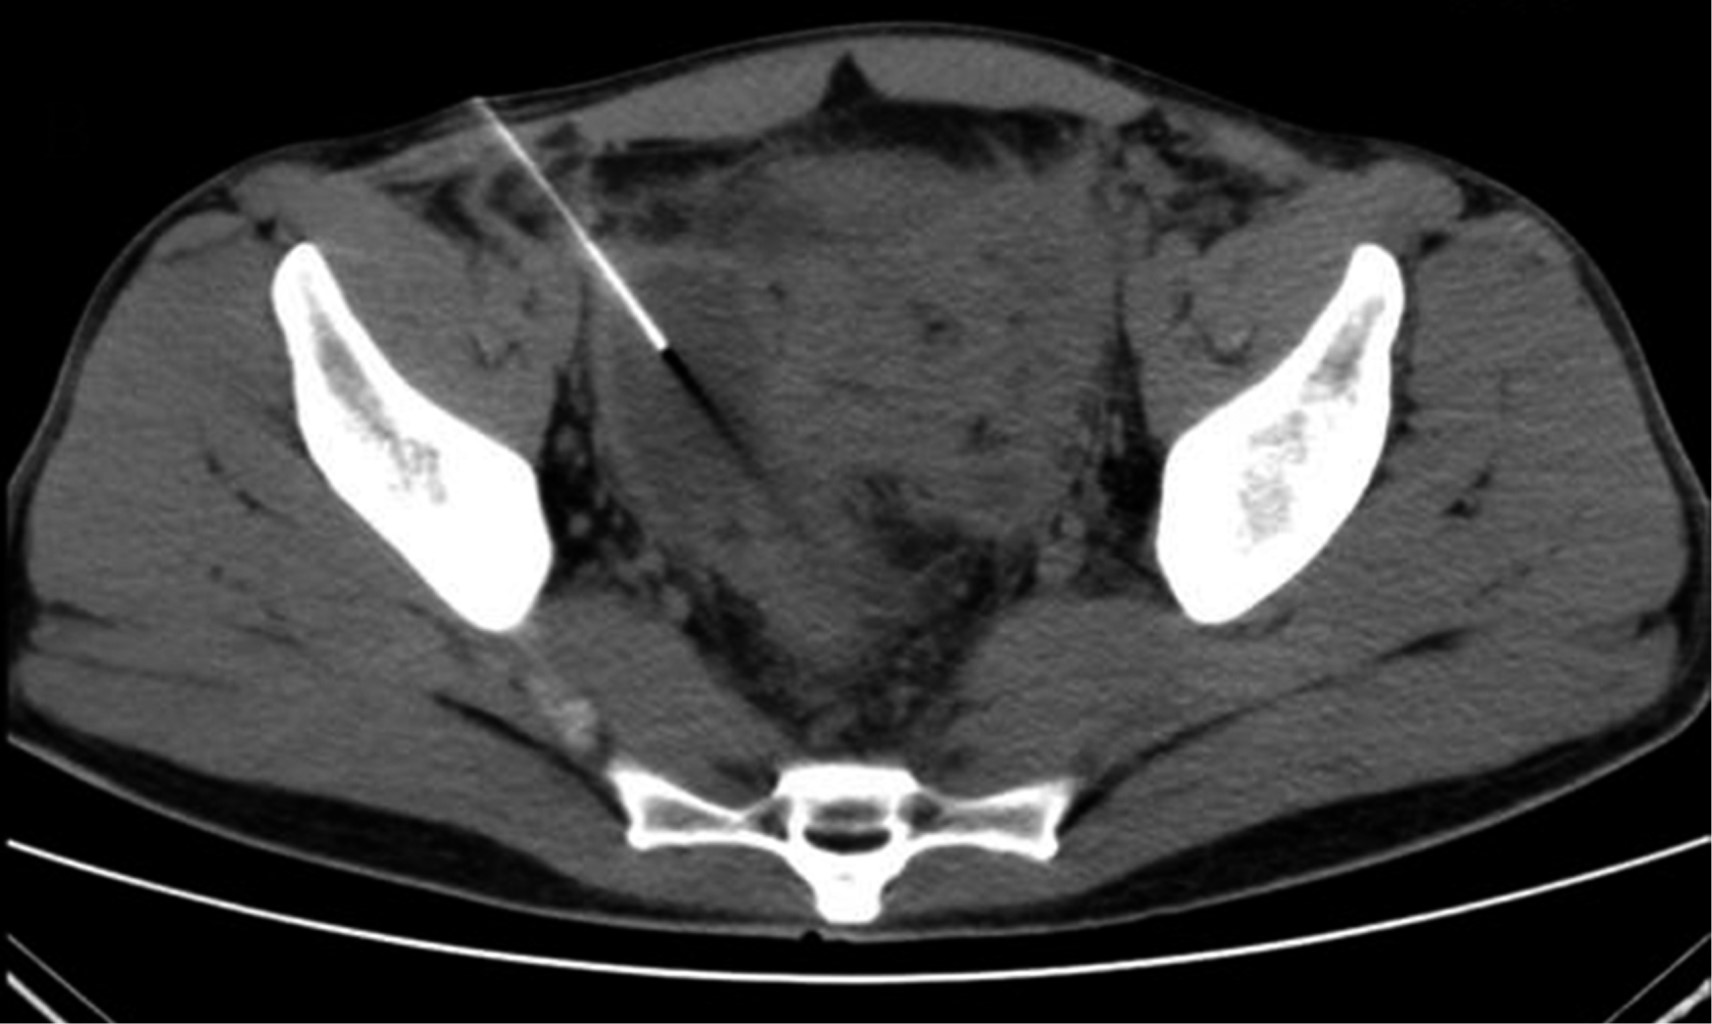

The CT scan of abdomen and pelvis with IV contrast showed free fluid in the right parieto-colic, intestinal interloop and peri-cecal slides. The cecal appendix with a diameter of 14 mm and thickening and enhancement of its wall was seen. A supra-vesical collection with extension to the right iliac fossa measuring 55 × 75 × 41 mm with a calculated volume of 88 cm3 (Figure 1) and another in the cul-de-sac with extension to the left iliac fossa measuring 60 × 57 × 70 mm with a volume of 125 cm3 were observed. Ultrasound-guided puncture with tomographic control of both collections was decided to perform (Figure 2), draining 70 and 120 cm3 of purulent fluid, respectively. Two Dawson Mueller® 10.2 Fr drains were left, one in the right iliac fossa and the other in the cul-de-sac zone. Broad spectrum antimicrobial management was started with meropenem 1 g iv every eight hours and vancomycin 1 g iv every 12 hours. He was left fasting for two days and parenteral nutritional support was started for three days with Oliclinomel® solution. The aerobic culture grew Streptococcus constellatus sensitive to ertapenem, so antimicrobial coverage was changed to ertapenem 1 g iv every 24 hours and vancomycin. The patient remained clinically stable, with no evidence of systemic inflammatory response and a progressive decrease in abdominal pain intensity. A control CT scan on his third hospital day (Figure 3) showed a significant decrease of fluid inside the collections. The right drain was removed on fourth day, with a total output of 10 cm3. Inflammatory markers showed a progressive decrease during his hospital stay. Final lab test results showed a white blood cell count of 9.9 10?3/μl, segmented neutrophils 67%, band forms 0% and a CRP of 4.05 mg/dl. The left drain was removed prior to hospital discharge on the ninth day of stay with a total output of 82 cm3. No interval appendectomy was performed during his follow-up because, based on age, history and imaging studies at diagnosis, the probability of neoplasia was considered low according to existing literature recommendations.

Figure 3